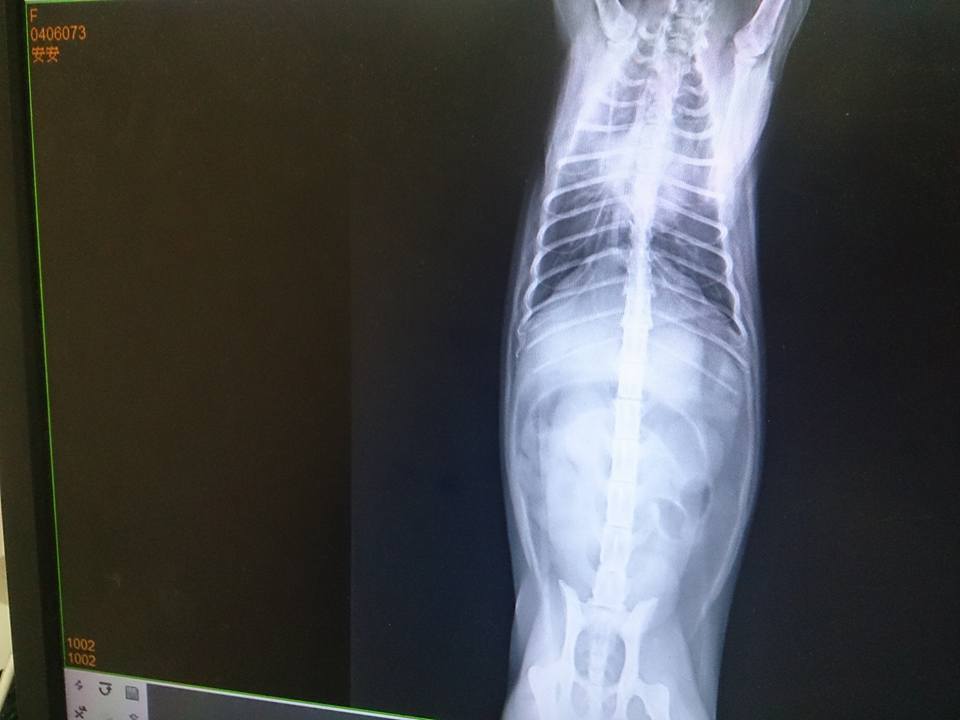

6/23進行了抽血檢驗、照X光、尿檢、糞剪、梨形鞭毛蟲檢查...等

排除傳染病引起的腹瀉和嘔吐,比較有可能是急性病毒感染,

給與靜脈抗生素和皮下止吐劑。